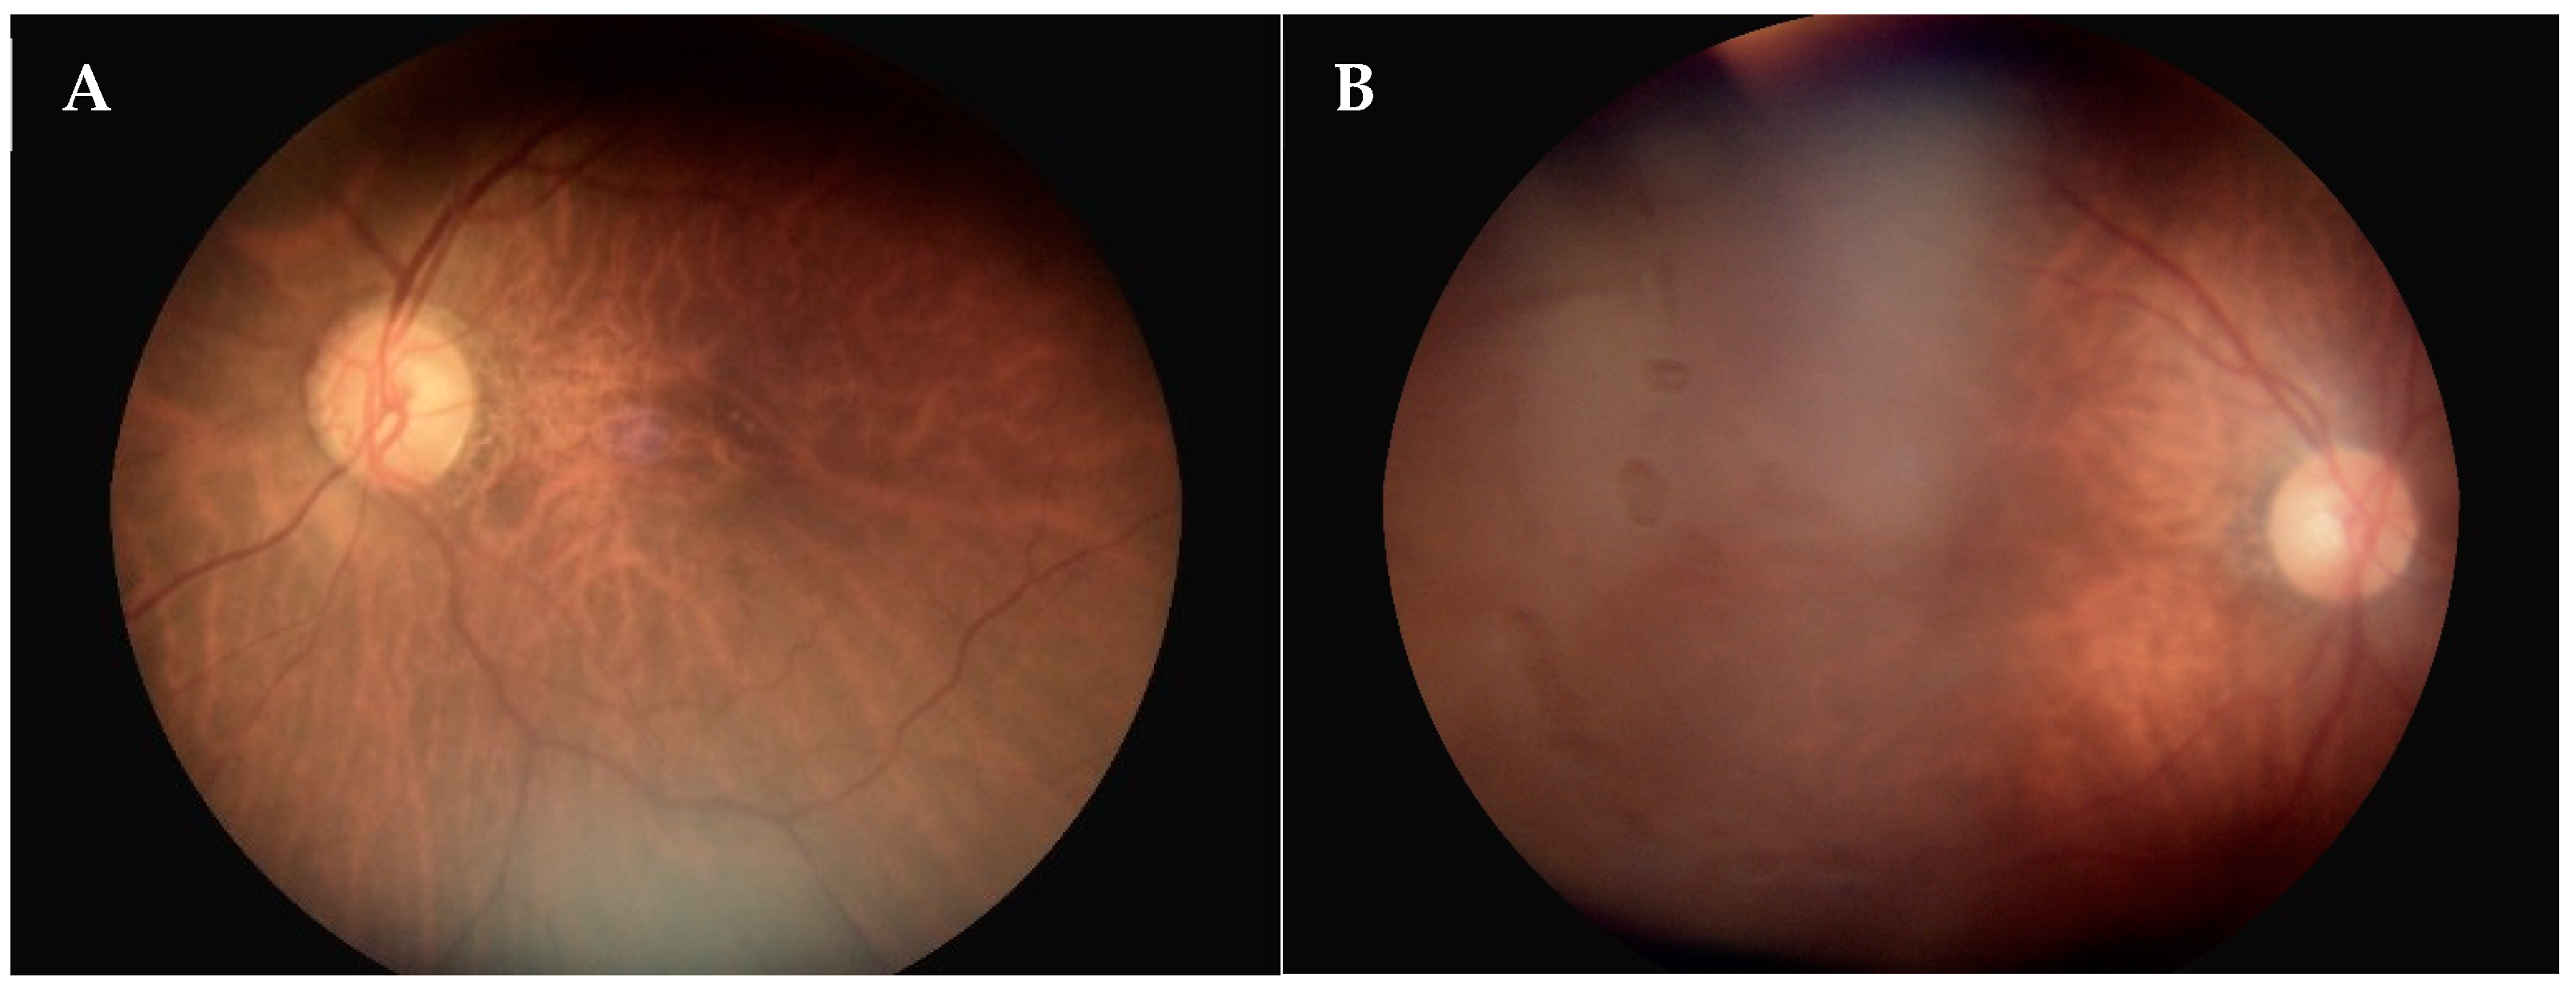

3.3. Evaluation of Fundoscopy Image Quality

3.4. Diagnostic Concordance of the Referrals